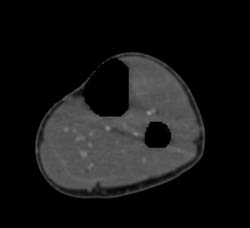

Stab Wound With Hematoma